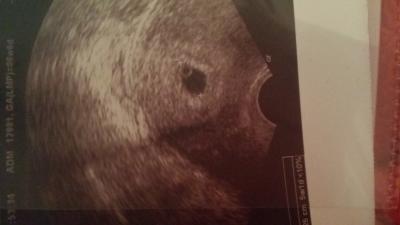

Hallo bin eigentlich 6+6 ssw war vor 3 tagen beim Arzt da konnte man nur die fruchthöhle sehen. Heute hatte ich wieder einen termin man konnte wieder kein embryo sehen nur einen dottersack. Meine ärztin meint das ich erst in der 5. Woche bin also heute 5+1. Zudem wurde ich vor 3 wochen von der galle operiert mit vollnarkose&546; Ich mache mir richtig sorgen ist das normal mein hcg wert ist gestiegen alles sieht soweit "normal" aus nur das Kind kann man nicht sehen und auch kein herzschlag..

Bild zu nur dottersack zu sehen! - Schwanger - wer noch? Rund um die Schwangerschaft

Weißt du denn wann dein Eisprung war? Es klingt so, als sei er später gewesen als du denkst und du noch nicht so weit bist. Denn wenn a) das HcG sich normal entwickelt und b) ein Fortschritt im US zu sehen ist, sind das doch gute Zeichen. Für Frauen mit späteren Eisprüngen funktioniert die Methode der Berechnung von den Schwangerschaftswochen ab dem ersten Tag der letzten Periode nämlich nicht. Das Bild sieht doch gut aus. Die Fruchthöhle ist schön begrenzt und auch der Dottersack ist gut zu sehen und rund. Ich bin kein Arzt, aber mein Laienauge findet es gut